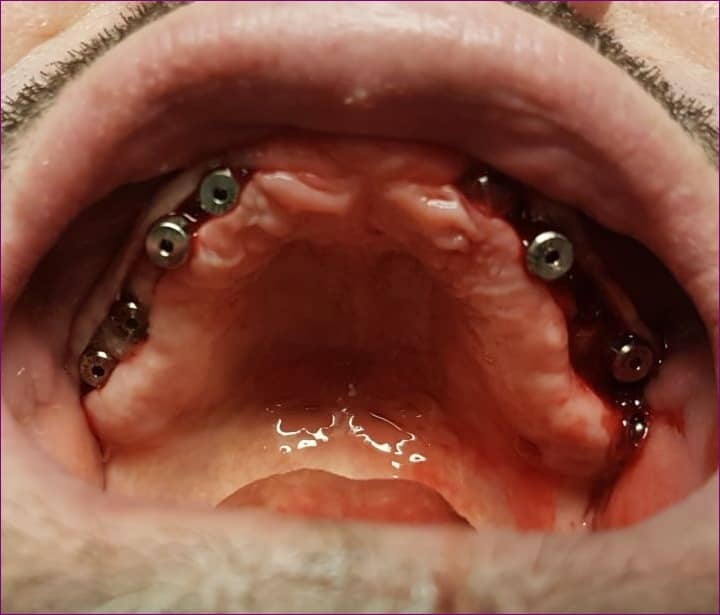

A fogpróbán tapasztaltak és megbeszéltek alapján a fogtechnikai labor elkészítette a cirkóniumvázat. Ez még leplezés nélküli nyers váz, viszont orvosi szempontból igen fontos fázis, mert a készülő csavarozható hídpótlás pontossága ilyenkor ellenőrizhető.

A vázpróbán vannak, akik némileg meghökkenve szemlélik a nyers vázat, mivel az még nemigen hasonlít a végleges pótlásra.